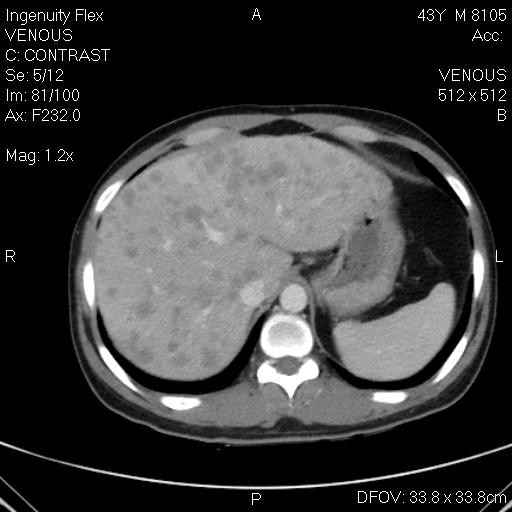

CT-bụng-hemagioma gan (P)